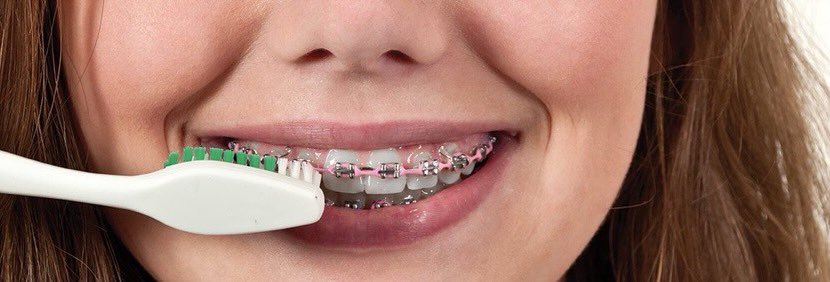

التهاب اللثة:(١٠)

الوقاية:

٩- الاشخاص الذين يستعملون الأجهزة التقويمية يجب أن يراعو عناية فائقة بالأسنان واللثة لوجود اجهزة يعلق بها كمية أكبر من البلاك وبالتالي تضاعف عدد البكتيريا المسببة للتسوسات والتهابات اللثة